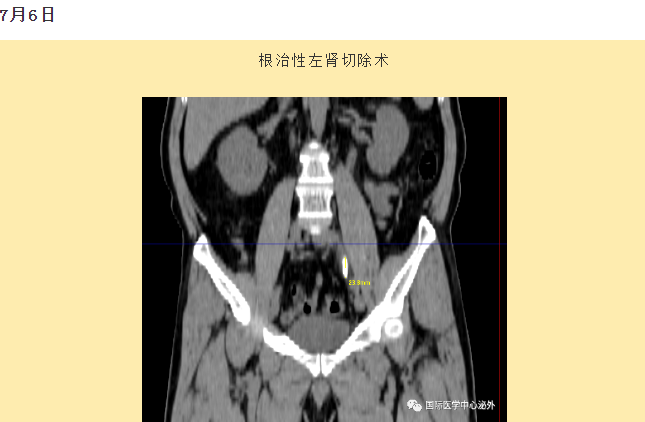

西安國際醫(yī)學中心醫(yī)院順利完成了達芬奇Xi(第四代)機器人裝機。7月6日—7月15日,泌尿外科成功完成了達芬奇Xi(第四代)機器人手術6例,標志著科室微創(chuàng)外科邁入新時代,造福萬千患者。